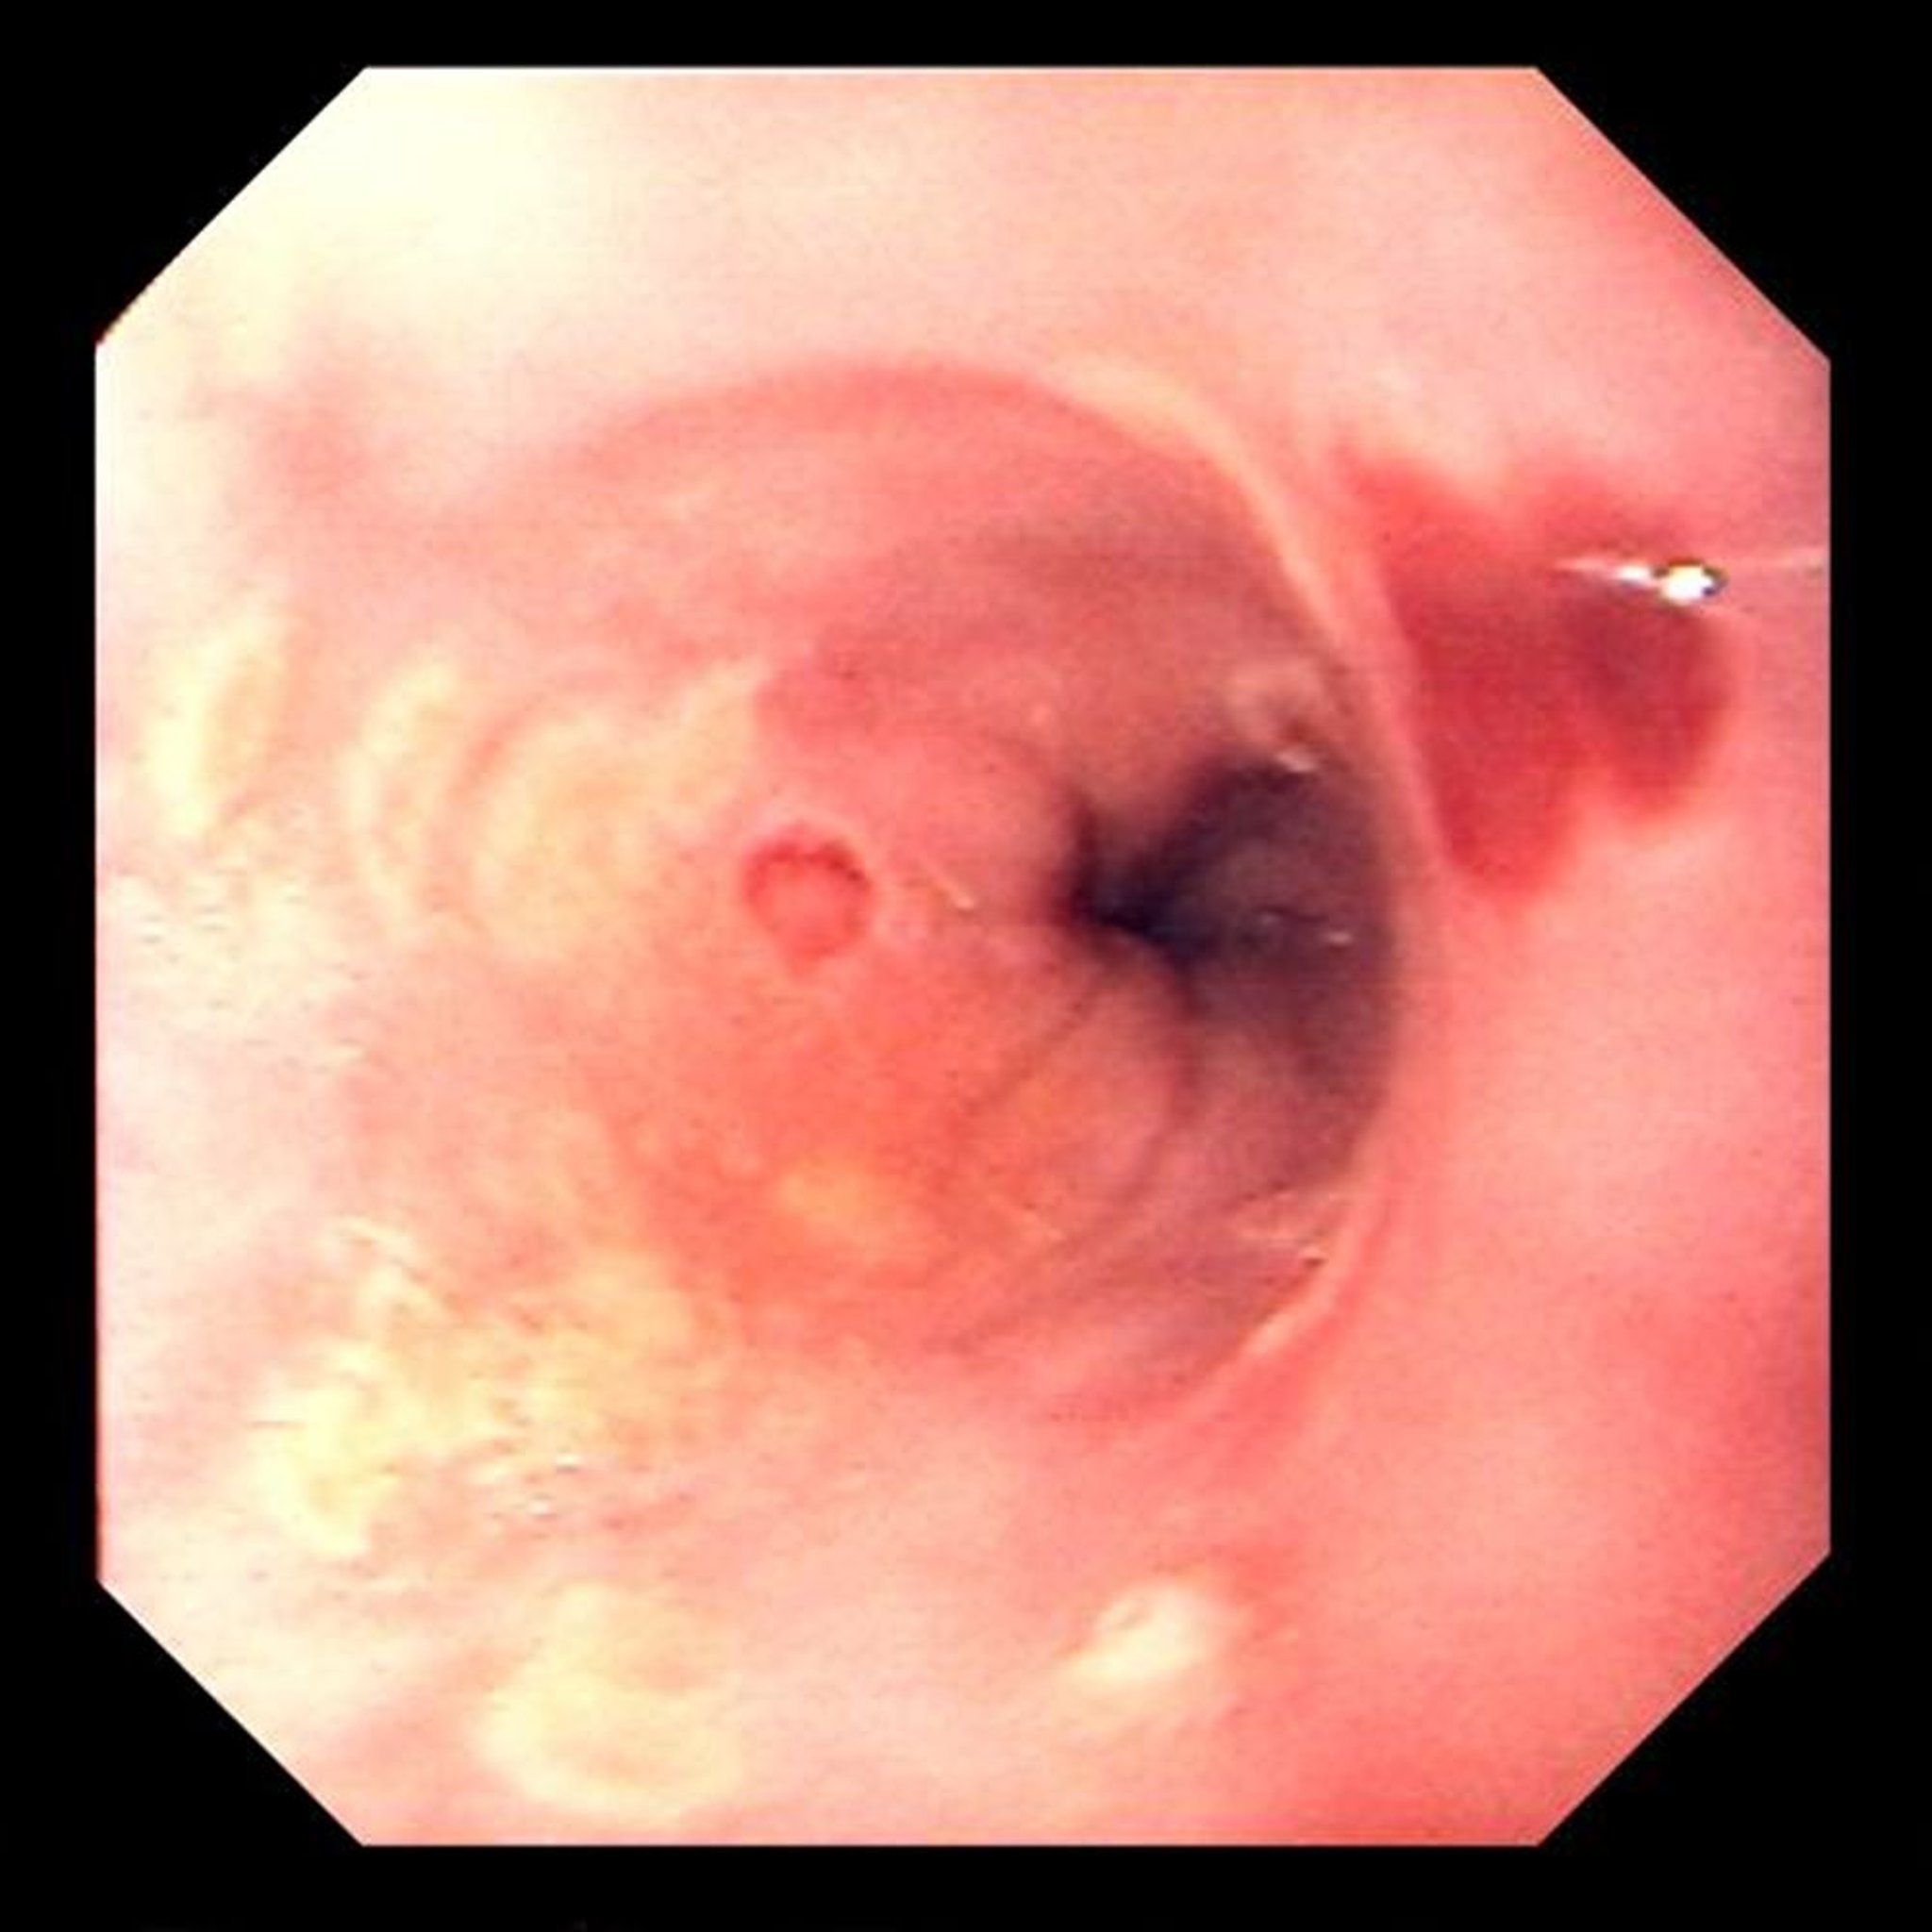

Esofagite por Herpes simplex

As ulcerações focais são típicas da esofagite pelo vírus da herpes simples.

Image provided by David M. Martin, MD.